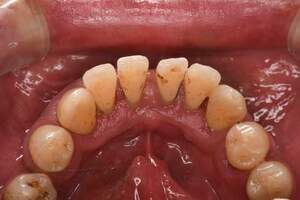

歯石除去

治療前

治療後

| 年齢 | 25歳・男性 |

| 主訴 | 歯石をとりたい・検診 |

| 治療内容 | 各種検査・歯石除去 |

| 治療期間 | 60分 |

| 費用 | 初診料3,000〜4,000円前後 +歯石除去約1,000円 |

| リスク・副作用 | ・処置後に歯がしみることがあります。 ・歯と歯の間に隙間ができるので、息が漏れ発音しにくいと感じることがあります。 ・歯ぐきの炎症が軽減すると歯ぐきが引き締まり、歯が長く見えることがあります。 |

| 担当者所見 | 前歯の裏側にすぐに歯石が溜まってしまいザラザラして気になるとご相談いただいたので適切な歯ブラシの当て方とフロスの通し方をお伝えさせて頂きました。 |